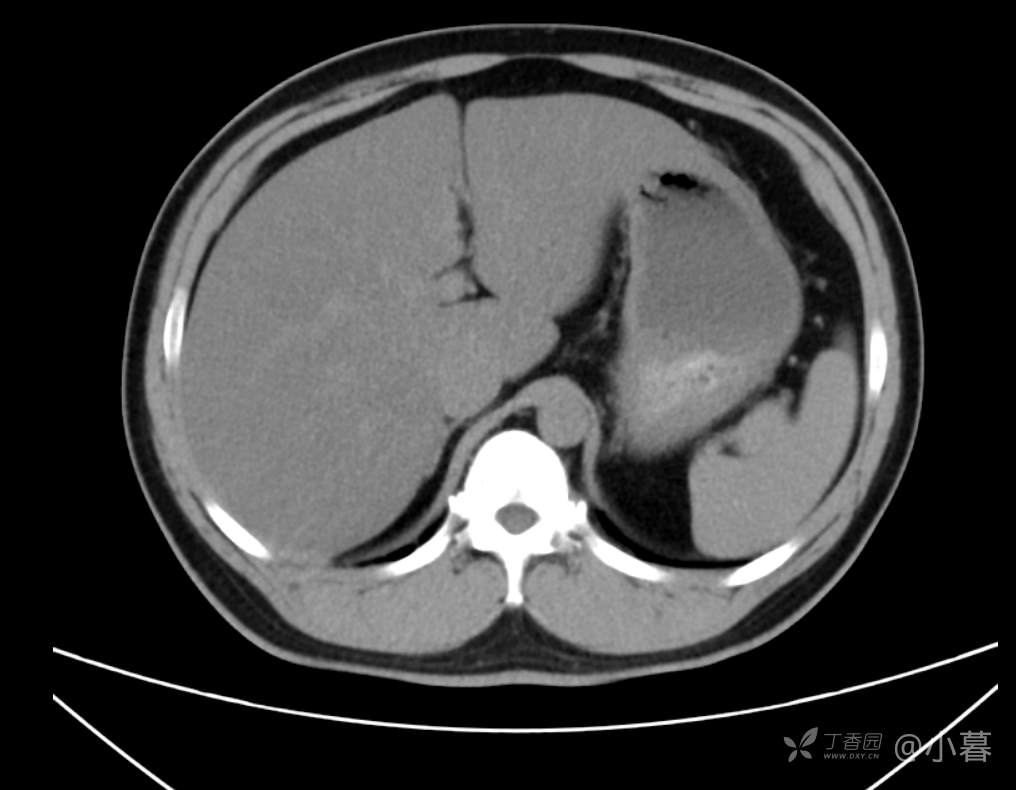

双肾超声无异常,无浆膜腔积液,体型尚正常,无腹型肥胖,轻度脂肪肝